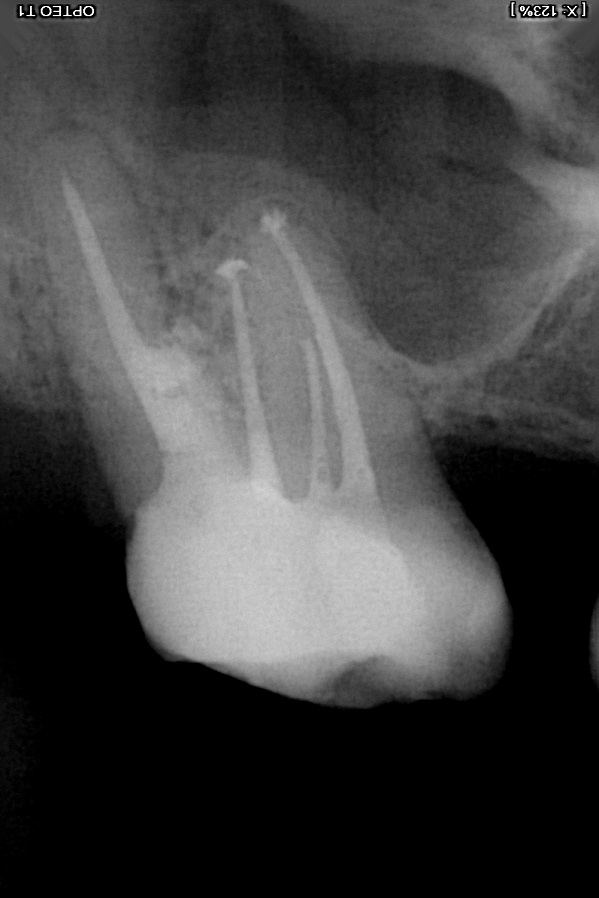

afijn vanmiddag naar de tandarts geweest en op de foto zag de tandarts ineens dan mijn wortel was opgelost. ze voelde ook met een haakje en had daar aan de achterkant wel wat diepe pockets. ze dacht aan een breuk in de wortel maar ik heb geen last met kauwen erop. alleen als ik met mijn tong op het kaakbot achter de kies druk dan voel ik wat. .

ik heb even een foto erbij voor Tandarts Richard .wat kunt u concluderen aan de hand van deze foto?

Tandarts_Richa…

idd lijkt op wortel resorptie. Element is helaas verloren. Oppassen voor mogelijke Antrum perforatie ( verbinding met neusholte) met verwijderen aangezien bot erg dun lijkt. Weet niet hoe de rest v h gebit eruit ziet.. maar nadenken over vervanging.

tingobop

Ik heb dan ook nog een vraag over de kies 17 waar ik de foto van gepost heb. ik snap de foto zelf niet zo goed. kunt u mij eens uitleggen wat er precies te zien is? voor zover ik kan zien is er een flink stuk van de wortel weg waar het gebied zwart is en niet grijs. maar het wortelkanaal waar de vulling zit staat er nog gewoon. hoe kan dit gezien alles er rond heen weg is?

eigenlijk had de tandarts dit gat al gelijk moeten dichten maar die had geen microscoop en wilde de kies niet meer aanraken. ik zie wel op de foto waar de wortel onderbroken is precies zit waar de kies in het verleden is geperforeerd. zie andere foto van direct na de endo 10 jaar geleden.